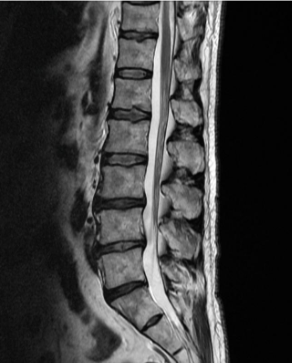

허리디스크는 디스크가 터져서 신경을 누를 경우 생기는 것으로 보통 4,5번에서 많이 발생하고 디스크가 터진 양이 적다면 터진 순간부터 수분이 날아가면서 양이 많이 없어지는데 그렇지 않고 양이 많을 경우 극심한 통증이 생깁니다.

통증이 덜한 환자들은 재활 , 물리, 약물치료 등을 통해 진행하지만 특정 원인이나 흘러나온 디스크가 신경을 많이 눌러 극심한 통증이 있다면 빠른 수술을 진행하는 것이 좋습니다.

허리디스크를 정확하게 진단하기 위해서는 엑스레이로는 힘들며, MRI를 통해 검사해야 정확하게 볼 수 있습니다.

MRI가 몸에 좋지 않지만 허리 통증으로 엑스레이만 진행 할 경우 오진이 많아 지속적인 통증이 계속 된다면 허리디스크를 의심하고 MRI 검사를 한번 받아보시길 권유드립니다.